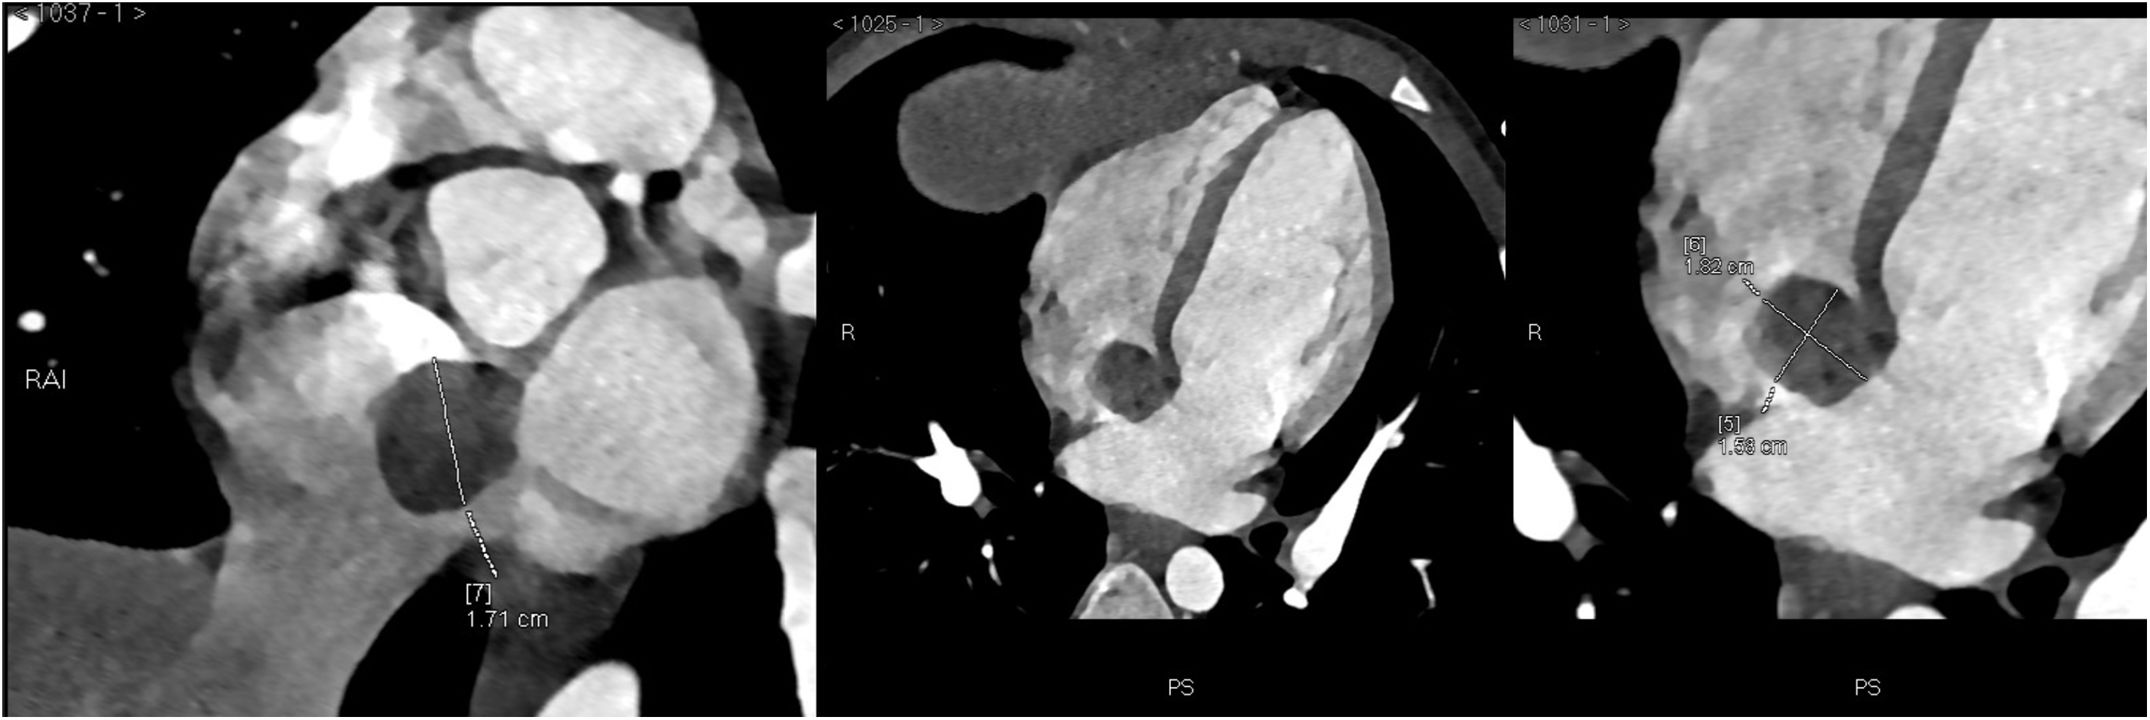

Presentación del casoMasculino de nueve años el cual es derivado por la presencia de soplo cardiaco. A la exploración se ausculta soplo sistólico expulsivo GII/VI en foco pulmonar sin irradiaciones, segundo ruido normal. En el ecocardiograma se observa masa intracardiaca quística en la aurícula derecha justo en desembocadura del seno coronario. Por lo que se solicita angiotomografía en la cual se reporta lesión quística intracardiaca en aurícula derecha con base en el septum interatrial por detrás del anillo tricúspideo y arriba del ostium del seno coronario, el quiste es ovalado de bordes lisos y bien definidos mide 17x16x18mm en sus ejes craneocaudal anteroposterior y transverso respectivamente con densidad promedio de 44 UH que sugiera componente hemático con un volumen aproximado de 2,5cc (figs. 1 y 2). La lesión no infiltra a la aurícula izquierda. Se presenta en sesión médica aceptándose para resección por accesos mínimos.